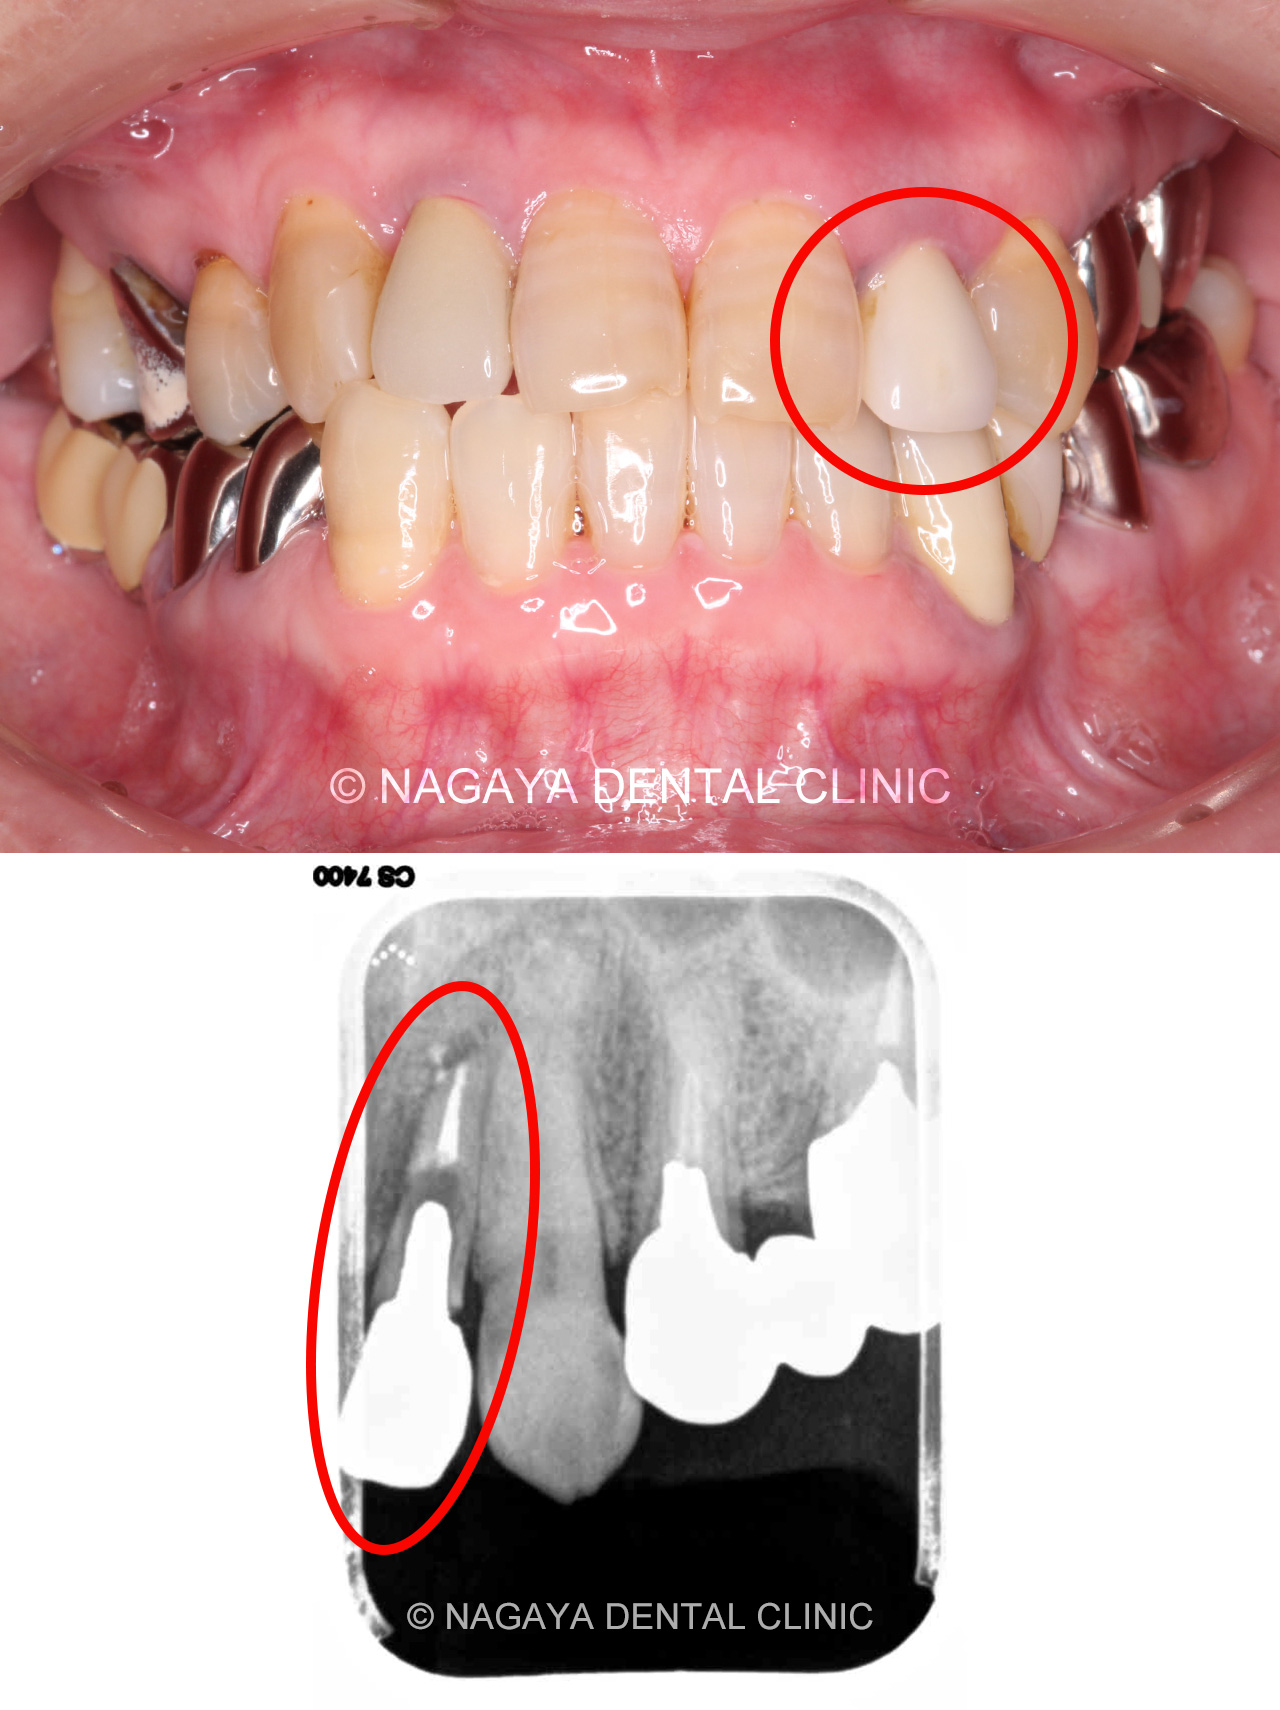

| 主訴 | 時々腫れる |

| 治療方法 | インプラント |

| 治療の説明 | 歯根が破折していた為、診断の結果抜歯が必要となりました。 患者様のご希望で、歯のない部分はインプラントによる治療を行いました。 クラウン(被せ物)は、ジルコニアセラミックスを選択された為、より天然の歯に近い形になりました。 |

| 治療期間 | 8ヵ月 |

| 副作用(リスク) | インプラント手術後は、出血、腫れなどがおきる場合がありますが、時間経過とともに治癒します。 また、喫煙、糖尿病、加齢、清掃不良などに伴いインプラント周囲の骨に炎症が起こり、再治療が必要になるケースがあります。 |